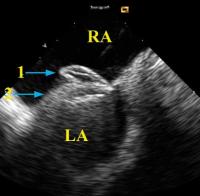

Figure 5: Device closure of a patent foramen ovale guided by intracardiac echocardiography with the AcuNav )(TM)-catheter placed in the right atrium and retroflexed into a short-axis orientation. Typical attitude before the Amplatzer (TM)-PFO occluder is removed from the cable. LA = left atrium; RA = right atrium; 1, right umbrella of Amplatzer (TM)-PFO occluder; 2, left umbrella of Amplatzer (TM)-PFO occluder

Keywords: Amplatzer-PFO-OccluderAmplatzer-PFO-OccluderAtriumAtriumCatheterechocardiographyEchokardiographieForamen ovaleForamen ovaleKatheter